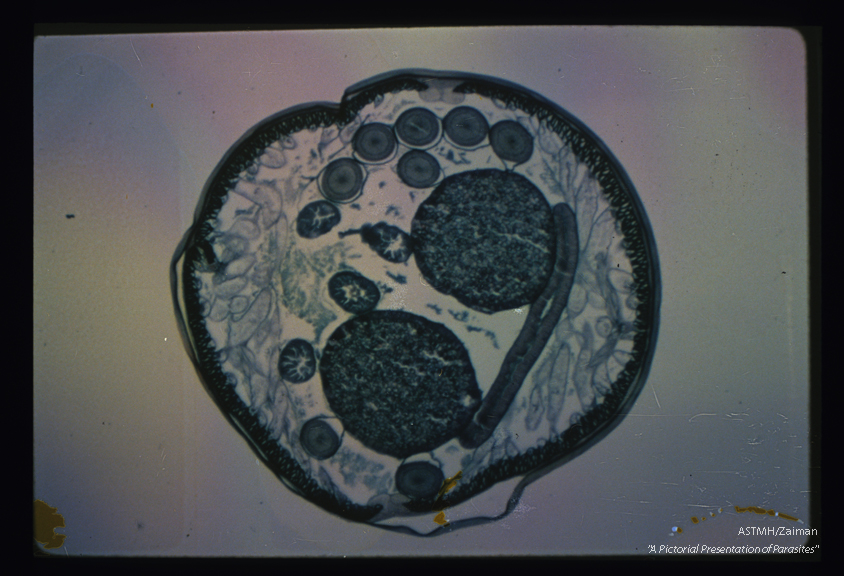

Cross section of an adult female. The outer cuticle is partially detached from the parasite at 12 o'clock. Below it, one can see the hypodermis and musculature. Lateral lines are visible at 12 and 6 o'clock. Central to the musculature, the flattened tube is gut, the round tubes are reproductive structures. The large round tubes are egg-containing uteri, the others are sections through ovaries and oviducts.

Ascaris lumbricoides

Description: Cross section of an adult female. The outer cuticle is partially detached from the parasite at 12 o'clock. Below it, one can see the hypodermis and musculature. Lateral lines are visible at 12 and 6 o'clock. Central to the musculature, the flattened tube is gut, the round tubes are reproductive structures. The large round tubes are egg-containing uteri, the others are sections through ovaries and oviducts.